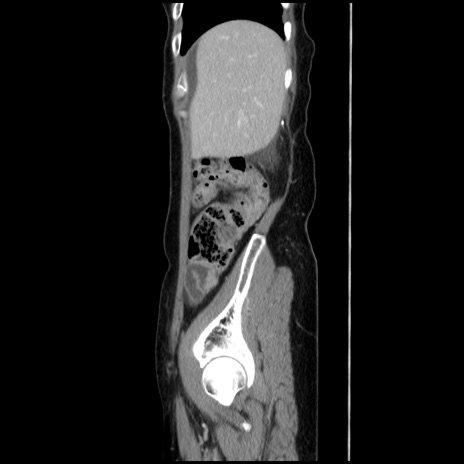

症例32(矢状断像)

【症例】40歳代 女性

【主訴】上腹部痛、嘔気・嘔吐

【現病歴】約9時間前頃から急に上腹部痛、嘔気、嘔吐が出現。改善しないため救急要請。

【既往歴】子宮頚癌(広汎子宮全摘術、放射線療法)、腸閉塞

【身体所見】腹部:平坦、軟、腸雑音亢進、上腹部を中心に腹部全体に圧痛あり。

【データ】WBC 8400、CRP 0.03